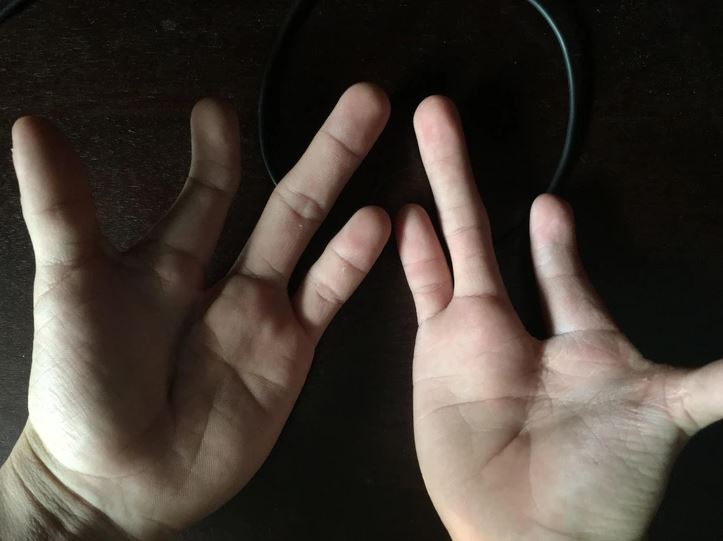

#19 Narodil som sa len s 3 prstami na každej ruke. So silou modernej medicíny sa mi podarilo dostať na každú ruku ešte po jednom prste